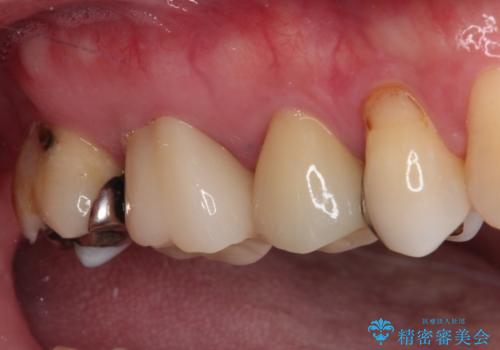

根管治療を行った後にオールセラミッククラウンにて補綴することとしました。

小臼歯は根管治療後に痛みが引きましたが、隣の大臼歯の痛みは引かなかったため、大臼歯も根管治療を行いました。

根管治療後に痛みは引き、半年後のレントゲン写真では根尖の病変の消失が認められました。